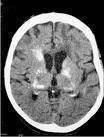

La tomografía axial computarizada sin contraste es fundamental para confirmar el diagnóstico del síndrome de Fahr y descartar otras entidades.

En 1930, Karl Theodor Fahr describió un paciente, con demencia de larga evolución, calcificaciones alrededor de los ventrículos laterales y ganglios de la base. Esta entidad se definió como enfermedad de Fahr. Entidad caracterizada por calcificaciones bilaterales, generalmente simétricas, con mayor compromiso sobre los ganglios de la base.

Esta enfermedad está caracterizada por calcificaciones bilaterales y simétricas, en los núcleos de la base o en otras áreas cerebrales asociadas a trastornos neurológicos. Afecta por igual a ambos sexos y se presenta más frecuentemente hacia la edad media. Se caracteriza clínicamente por alteración del tono muscular y de la regulación de los movimientos voluntarios y automáticos.